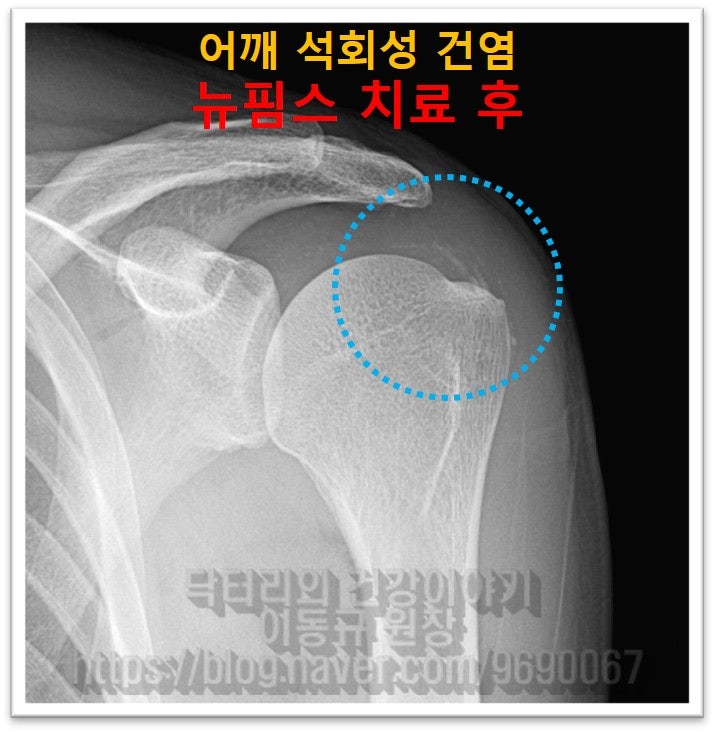

이렇게 상당히 큰 석회라도 충분히 비수술적 치료를 할 수 있습니다. 그래서 뉴핌스치료(석회분쇄흡입술)를 시행하였습니다.

남아있는 석회는 향 후 충격파 치료를 추가적으로 시행하여 흡수를 시키면 됩니다.

환자분은 시술하고 난 후 정말 거짓말 처럼 통증이 사라졌다고 좋아 하셨습니다. 석회성 건염은 크기가 크다고 수술해야하는 것이 아닙니다. 크기가 크더라도 충분히 비수술적으로 제거할 수 있습니다. 물론 비수술적으로 석회를 제거하기 위해서는 숙련된 기술과 충분한 경험이 있어야 합니다. 석회의 양상과 크기, 위치에 따라서도 석회분쇄흡입술이 달라질 수 있기 때문입니다.

석회가 잘 제거되지 않거나 힘줄의 손상까지 발생될 수 있으니 충분한 경험이 있는 의사에게 시술을 받으시는 것이 좋습니다.